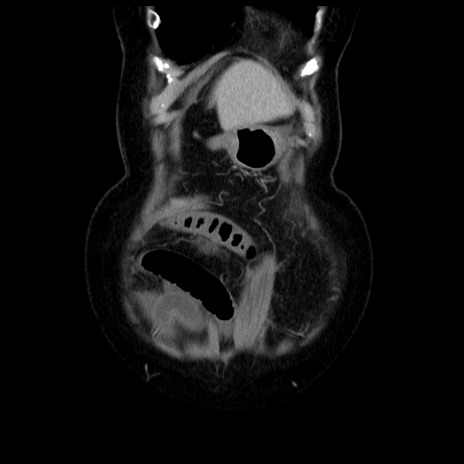

症例13(冠状断像)

【症例】70歳代女性

【主訴】腹痛、嘔吐

【現病歴】15時間程前(昨晩)より腹痛あり。今朝になっても症状の改善なく、嘔吐あり。腹痛も増悪あり、救急外来受診。

【既往歴】子宮癌全摘術後

【身体所見】意識清明、BP 121/72mmHg、P 74bpm、SpO2 100%(RA)、腹部:平坦・軟、腸雑音ほぼ聴取せず。下腹部・心窩部・臍左上に圧痛あり。反跳痛なし。

【データ】WBC 10600、CRP 0.15